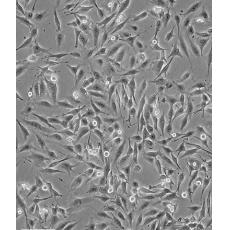

MDA-MB-435

中文名稱 人乳腺癌高轉移細胞

組織來源 乳腺癌

細胞種屬 Homo sapiens, human

生長特性 loosely adherent with floating clusters

形態特征 epithelial

細胞描述 該細胞1976年建系,源自一位48歲患有乳腺癌女性的胸腔積液,但近來有研究證明該細胞被M14黑色素瘤細胞污染。